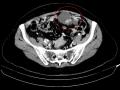

Biópsia por agulha grossa, guiada pela US, de recidiva peritoneal de carcinoma de ovário.

Aula sobre o diagnóstico de lesões tomográficas suspeitas de recidiva de carcinoma seroso do ovário e a biópsia por agulha grossa, guiada por ultrassonografia, de recidiva peritoneal sob a parede abdominal.